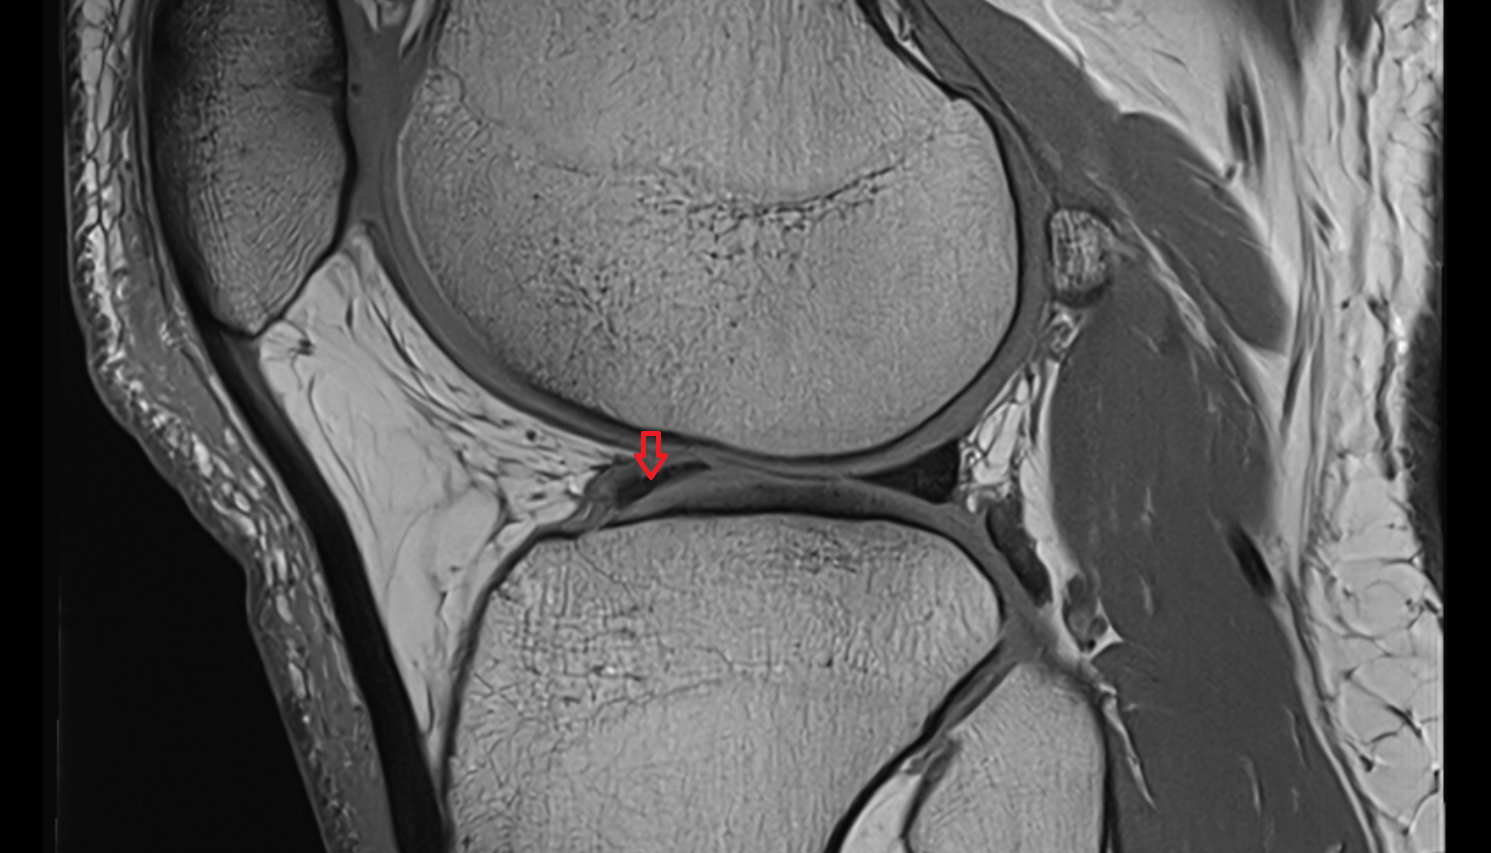

- Anterior cruciate ligament

- Posterior cruciate ligament

- Medial meniscus

- Lateral meniscus

- Posterior horn of medial meniscus

- Posterior horn of lateral meniscus